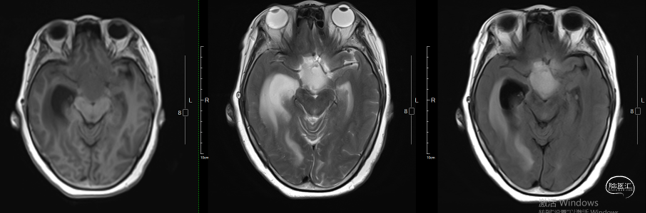

术前影像学资料

术前激素/电解质水平:术前皮质醇、性激素、促肾上腺皮质激素等垂体相关激素,电解质均未见明显异常。

术前诊断:1. 颅咽管瘤 2. 梗阻性脑积水

手术入路选择:患者病灶以囊性为主,病灶完全位于鞍上,病灶靠前,向前上方推挤,病灶主体位于中线。结合病灶实性及起源部位,以及病灶的性质,虽然经鼻具有视角广可直视,对于重要结构干扰较小的优势,常用于鞍内或鞍内-鞍上型;但是此病例主体位于鞍上,起源于垂体柄上部,开颅经额底纵裂入路能直视游离下丘脑边界,同时肿瘤上极未达到三脑室的穹顶,此入路可全切肿瘤,因此,选择开颅经额底纵裂入路。